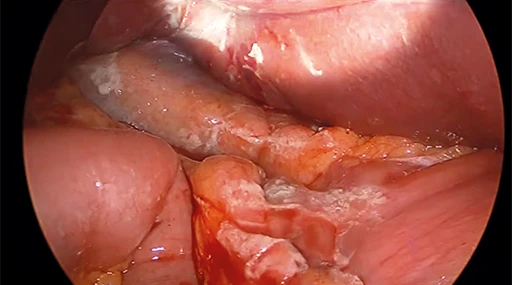

Questa testa telecamera avanzata è dotata della capacità di supportare sia l’imaging a luce bianca che a fluorescenza NIR, consentendo così la visualizzazione in tempo reale delle strutture marcate con ICG. È ideale per procedure oncologiche e vascolari in cui è essenziale una migliore differenziazione dei tessuti.

Cambiamento di colore (CS1 / CS2)

Senza cambiamento di colore (CS1 / CS2)

Strutture e imbarcazioni sono appena visibili, molte sfumature di rosso.

Con Color Shift (CS1 / CS2)

Migliore visibilità delle strutture e dei vasi, riduzione delle sfumature di rosso, colori fortemente contrastati.

Doppia modalità di imaging per la precisionechirurgica

Il controller AlphaSMART Cam+ consente di passare senza soluzione di continuità dalla modalità luce bianca alla modalità fluorescenza NIR, supportando la visualizzazione in tempo reale della perfusione tissutale, dei linfonodi e delle strutture biliari durante l’intervento chirurgico.